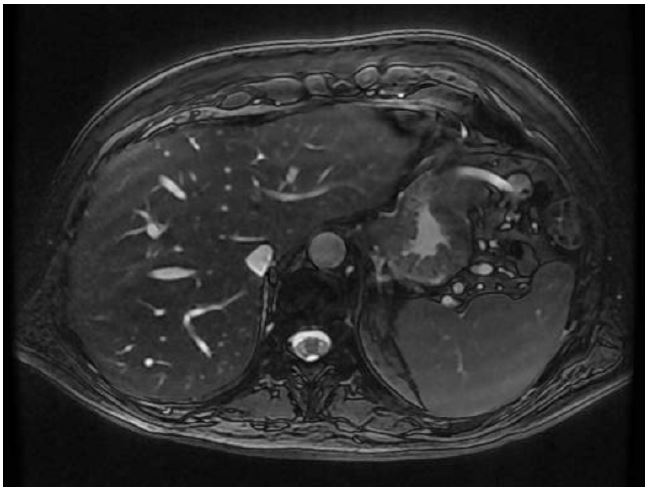

Diagnosis: In February 2022, a 70-year-old male presented with weight loss of 15 kg for approximately 3 months and consumptive symptoms. He had no past history of any chronic disease nor personal risk factors besides sporadic cigar smoking with a smoking index / pack years calculation which was non-significative. From February through July 2022, he did not seek nor receive medical attention. He continued symptomatic, prompting the need for extensive imaging studies. On July 2022, a Magnetic Resonance Imaging (MRI) was performed showing an Intraductal Papillary Mucinous Neoplasm (IPMNs) of the pancreas (Figure 1). During his evaluation, the patient refused further examination and treatment.

Figure 1: Imaging picture of the first Magnetic Resonance scan (MRI-T2 weighted) at the initial diagnosis showing at least two images: The first described at the tail of the pancreas, heterogeneous and hyperintense due to a small nodule, which measures 9 mm on its longest axis. The second at the distal edge of the pancreatic tail, with a thin wall, multilobulated with homogeneous hyperintense content on T2-weigthed, measuring 20×9 mm, which is dependent on the main pancreatic duct and causes dilation of the adjacent segment up to 4 mm associated with parenchymal atrophy.